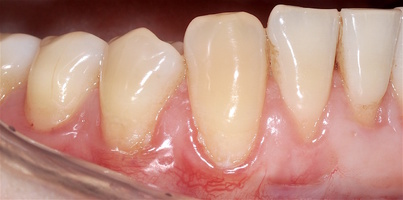

Во всех случаях применения аутотрансплантата и ТМО (dura mater) наблюдается сопоставимый положительный клинический результат по всем параметрам оценки рецессий десны (табл. 4). В случае нескольких зубов в области наиболее глубоких рецессий с наименьшими клиническими показателями имеет место сохранение класса рецессии не более первого класса (9 зубов) и глубиной не более 2 мм, 1.6 зуб — 3 мм.

В зарубежной литературе встречается также совокупный показатель эффективности лечения рецессий десны — процент закрытия корня зуба — отношение разница между конечным и исходным значениями глубины рецессии к исходному значению в процентах. Положительный результатом лечения является значение равное или более 80% [4]. Использование только показателя глубины рецессии десны для анализа эффективности лечения без учета остальных показателей (ТКД, ШКД, РРД, ЗДК) не дает полной картины результата и может быть применимо только в совокупности с другими показателями (рис. 6а-й).

Так в нашем случае процент закрытия корня зуба наблюдается больше 80% у 13 зубов. Менее 80% — у 11 зубов. Это связано с сохранением класса рецессии после лечения в области зубов с наибольшим классом рецессии и наибольшим показателем глубины рецессии. При этом средний показатель всех 24-х оперированных зубов — 83,1%. При этом среднее значение процента закрытия корня зуба для зубов с положительным результатом (более 80%) составляет 96,65%. Среднее значение для результатов менее 80% — 54,73, что связано с изменением глубины рецессий с 6 мм до 3 мм, с 4 мм до 2 мм и с 2 до 1 мм. При этом для аутотрансплантата и для ТМО результаты сопоставимы.